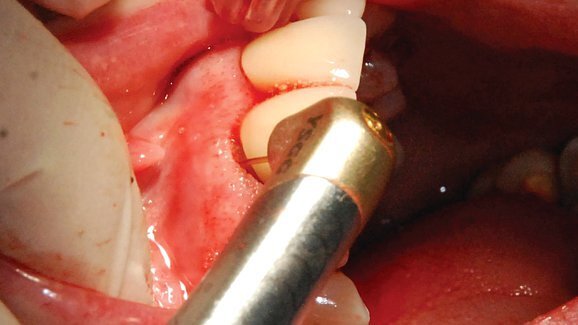

The lecture will take participants through the etiology and risk factors associated with periodontal disease, provide an overview of available and current treatment modalities, and demonstrate a minimally invasive technique using an Er,Cr:YSGG laser to achieve favorable outcomes with minimal adverse side effects.

During the one-hour course, participants will gain a better understanding of how lasers work on soft tissue and bone, of the use of Er,Cr:YSGG laser in periodontics for the management of periodontitis, and of the mechanisms through which the Er,Cr:YSGG laser can be effective in periodontal pockets. The speaker, Dr. Rana Al-Falaki, will also provide participants with an understanding of the requirements for periodontal regeneration and the use of the Er,Cr:YSGG laser in achieving this goal.